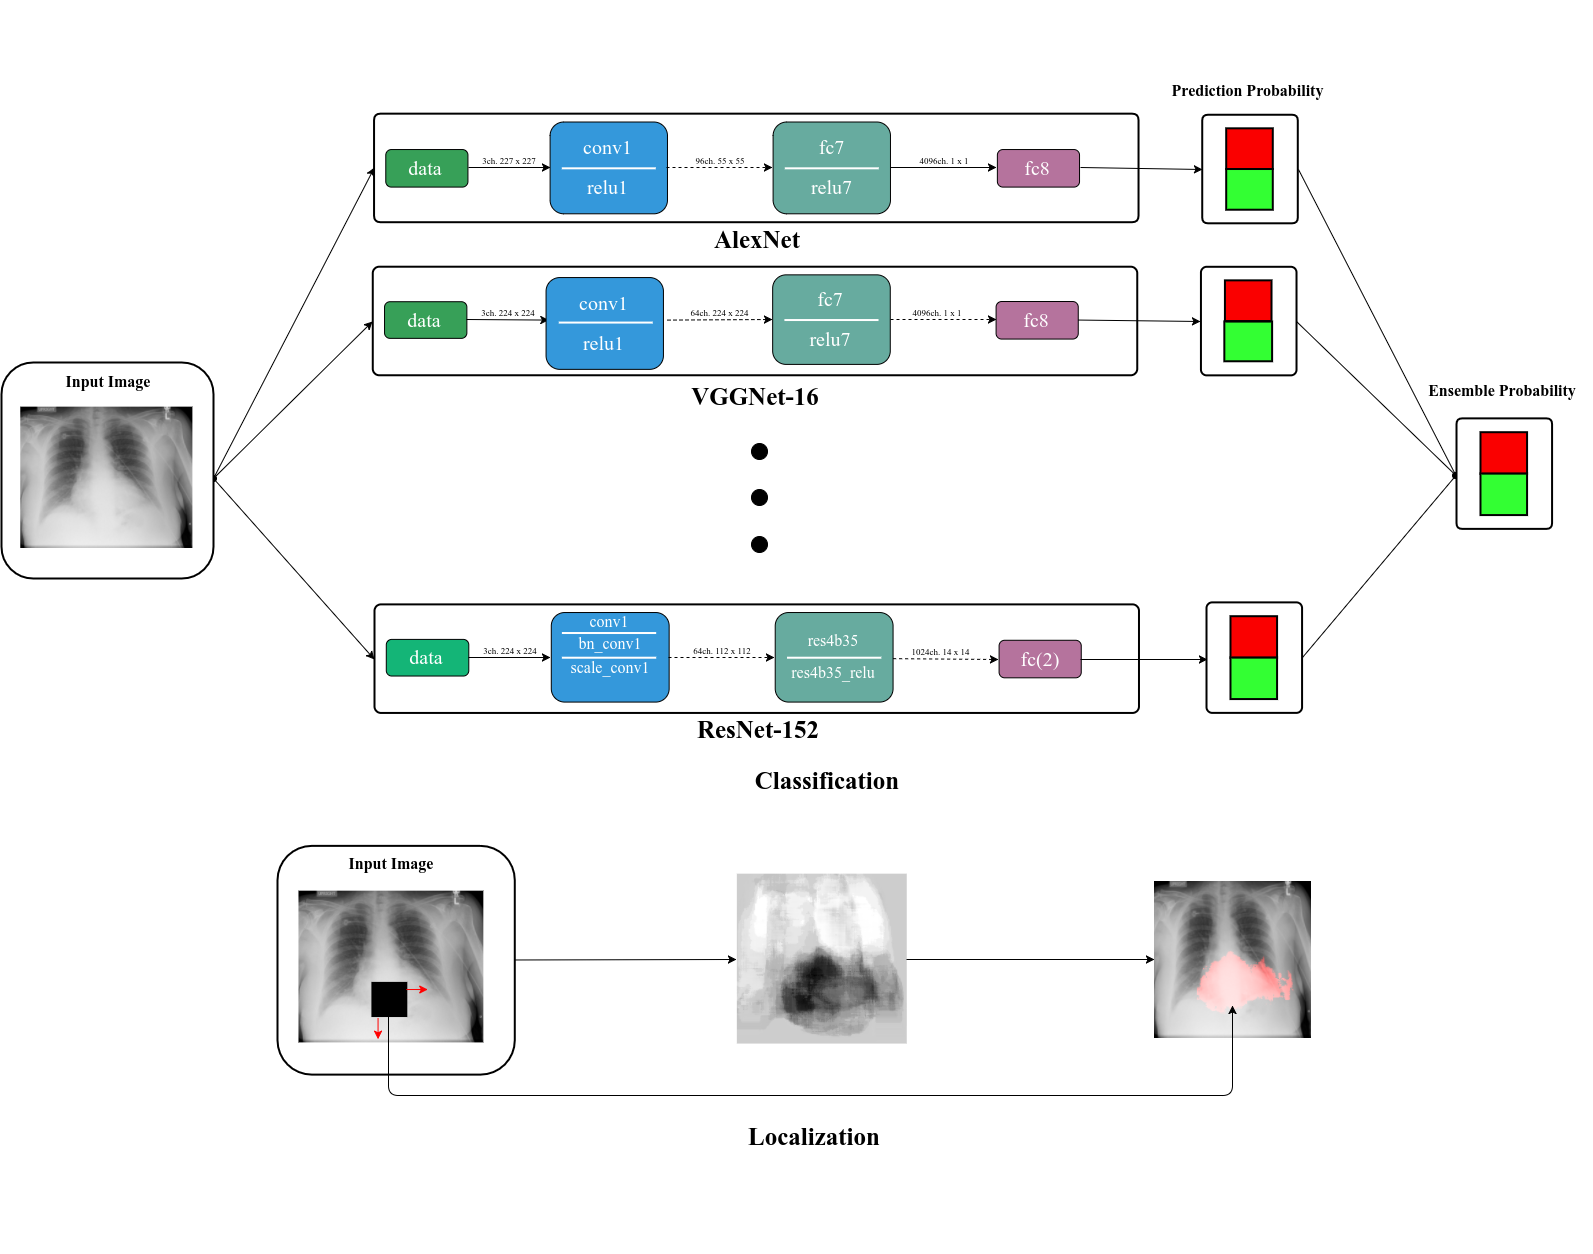

The overall classification scheme and localization scheme is visualized in Fig. 2. In summary, the classification scheme (top) is ensemble of different types of DCNS and the localization (bottom) is obtained from the overlapping occlusions.